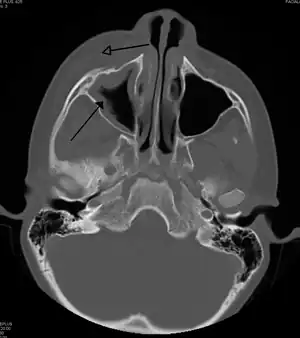

| A CT scan showing sinusitis of the ethmoid sinus | |

For sinusitis lasting more than 12 weeks, a CT scan is recommended.[53] On a CT scan, acute sinus secretions have a radiodensity of 10 to 25 Hounsfield units (HU), but in a more chronic state they become more viscous, with a radiodensity of 30 to 60 HU.[55]

CT of chronic sinusitis

CT scan of chronic sinusitis, showing a filled right maxillary sinus with sclerotic thickened bone.